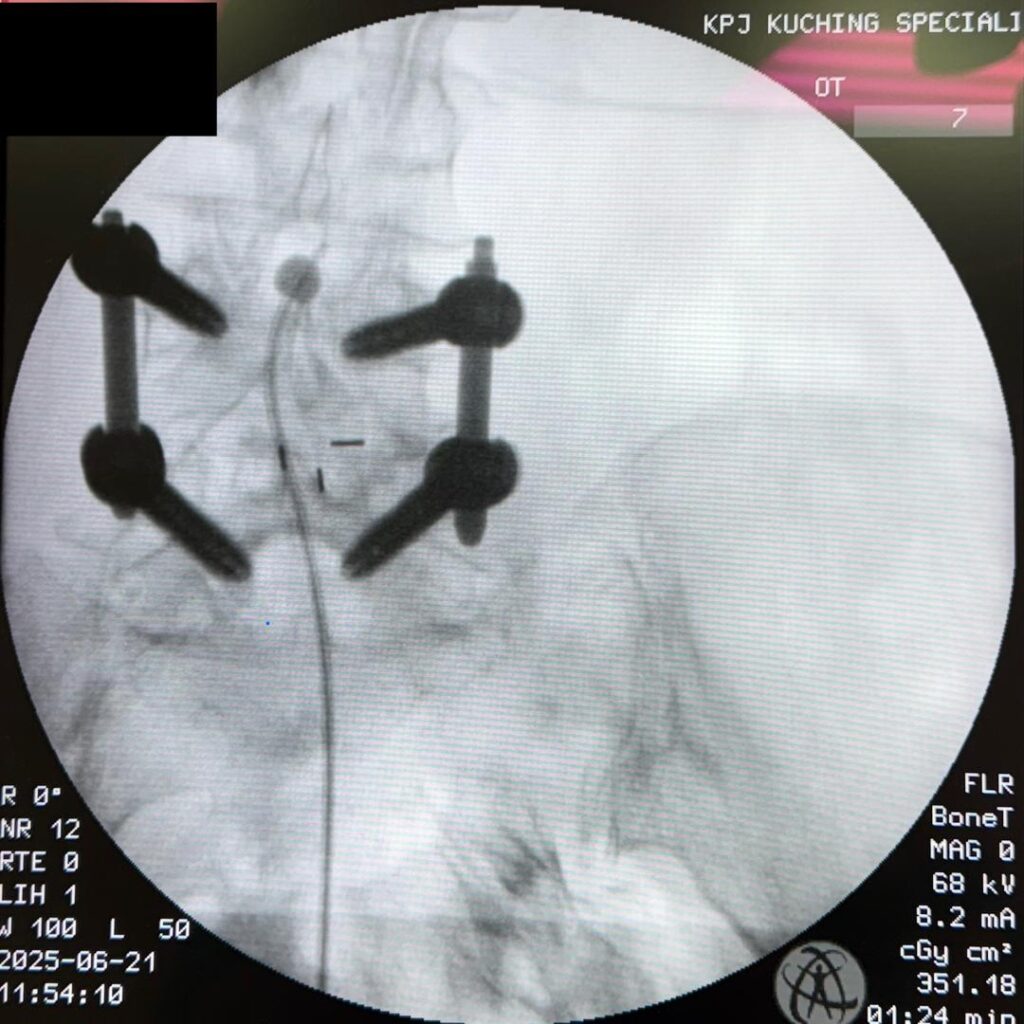

Dr. Chen Chee Kean, Interventional Pain Specialist and President-Elect of the Malaysian Society of Interventional Pain Specialists (MSIPP), performed the first procedure using an original device developed by Juvenui of South Korea. Under fluoroscopy (live X-ray) guidance, a small balloon is inserted into the spine’s epidural space. When inflated, it gently opens up the narrowed area, relieving pressure on the nerves and improving blood flow.